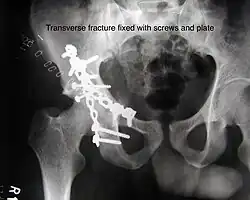

Transverse fracture showing upper iliac fragment, lower ischial and pubic fragment -

Transverse fracture fixed with screws and plate

| Transverse | In this variety of fracture, the innominate bone is broken such that the upper part consists of ilium with weight bearing dome and the lower part consists of ischium and pubic bones. It typically occurs when the injuring force is applied from the side, against the greater trochanter of the femur bone, as in a fall on the side or being hit on the side. This is a two part fracture, but though both columns are broken, it is not a true both-column fracture, as the weight bearing dome is still attached to main ilium.

In this variety of fracture, the innominate bone is broken such that the upper part consists of ilium with weight bearing dome and the lower part consists of ischium and pubic bones. It typically occurs when the injuring force is applied from the side, against the greater trochanter of the femur bone, as in a fall on the side or being hit on the side. This is a two part fracture, but though both columns are broken, it is not a true both-column fracture, as the weight bearing dome is still attached to main ilium. Depending on the level at which the fracture line passes in relation to weight bearing area, the transverse fracture is further subdivided into types:

X-ray visualization is best done in Antero posterior view and Iliac and obturator oblique views. In CT scan the characteristic feature is that the fracture line runs from front to back. CT scan also helps in identifying impaction of bone pieces and if there are pieces in the joint |